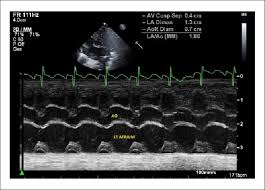

the following m-mode tracing:

d. provides no info regarding diastolic function status